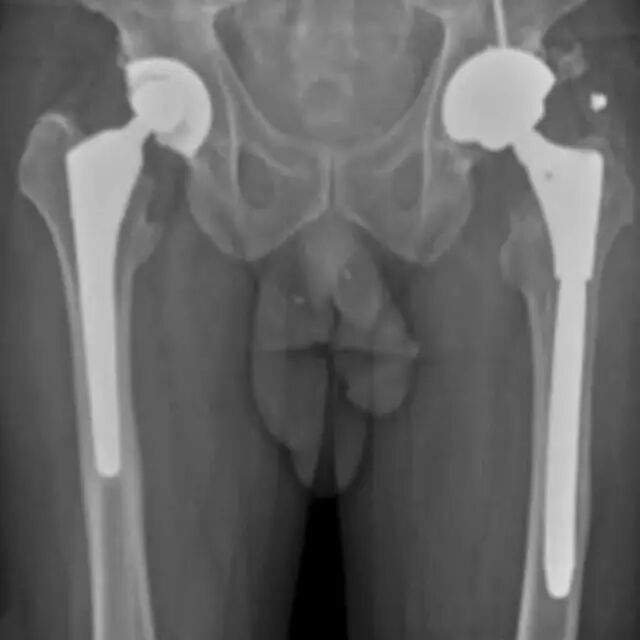

陷阱9:硬件放置后的骨折

骨折评估在硬件放置后的患者中是具有挑战性的,例如由于各种原因的骨折固定或关节置换所见[45,46]。密集重叠的金属密度可以限制硬件骨折或假体周围骨折的可视性。倾斜视图通常是有帮助的。诸如CT或MRI的横截面成像可以受到金属伪影的限制,并且应当在可用时使用修改的金属伪影减少协议来执行。硬件植入物改变宿主骨上的应力,导致应力屏蔽发生时的慢性骨丢失和应力集中的骨肥大。当经受创伤时,力倾向于集中在植入物和骨之间界面的位置。断裂通常在那些界面处开始,然后远离集中点传播。例如,髋关节植入物患者中的股骨骨折通常穿过股骨柄的尖端(图11)。通过具有内固定的骨的骨折通常穿过板的末端处的皮质。

图11A、B -54岁左侧全髋关节置换术的男性。A,骨盆正位片(A)和左侧髋部青蛙侧视图(B)显示股骨中轴延伸到股骨柄尖水平的倾斜骨折(箭头B)。